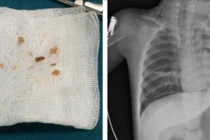

Ngày 23/7, Bệnh viện Đa khoa tỉnh Quảng Ngãi 2 cho biết đã bàn giao thi thể bệnh nhi L.N.A (2 tuổi, trú xã Kon Braih, tỉnh Quảng Ngãi) cho người nhà tổ chức tang lễ. Bé A. tử vong do hóc dị vật là hạt nhãn ở đường thở.

Bé gái 2 tuổi bị hóc hạt nhãn được các bác sĩ Bệnh viện Đa khoa tỉnh Quảng Ngãi 2 nỗ lực cứu chữa nhưng bất thành/Ảnh NLĐ

Tại đây, các bác sĩ Bệnh viện Đa khoa tỉnh Quảng Ngãi 2 đã nỗ lực cấp cứu nhưng bệnh nhi đã tử vong.